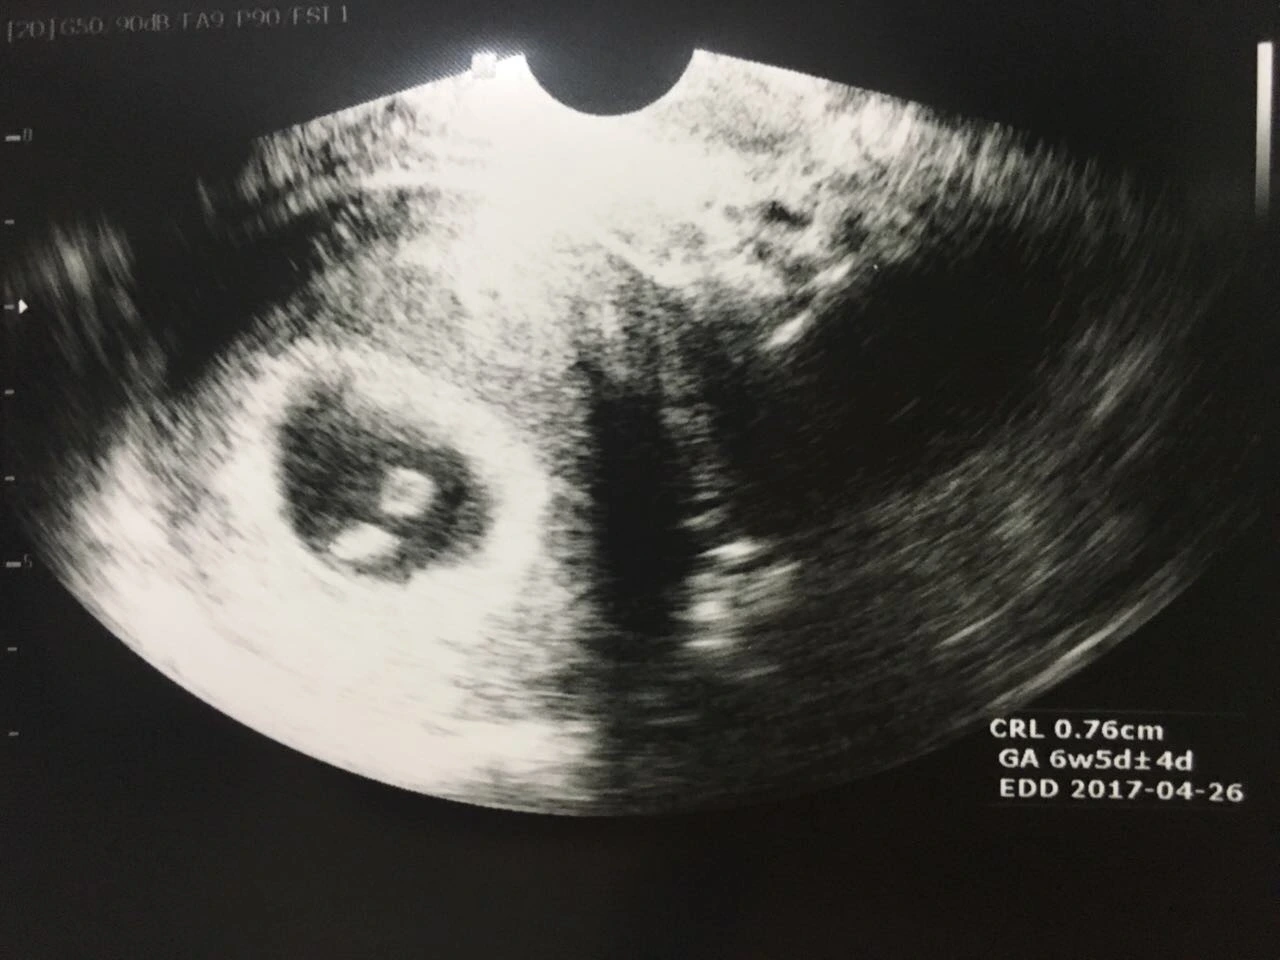

그리고 우리의 첫 만남.

아주 작은 콩알만한 너.

벌써 6주나 응큼하게 잘 자라고 있던 너.

쾅쾅쾅쾅 빠른비트의 심장소리를 가진 너.

태아소견 : Good!

출산예정일 : 2017년 4월 26일